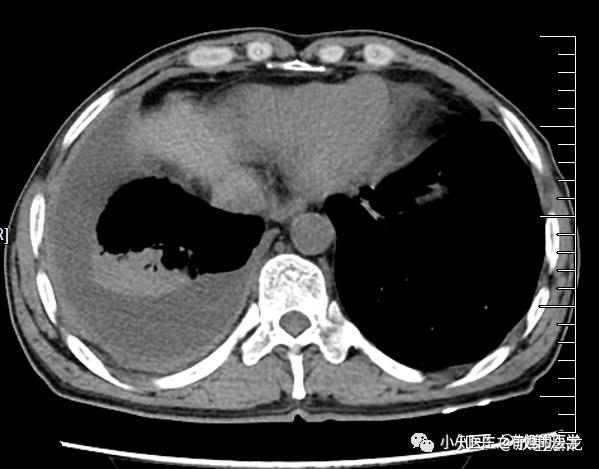

游离性胸腔积液